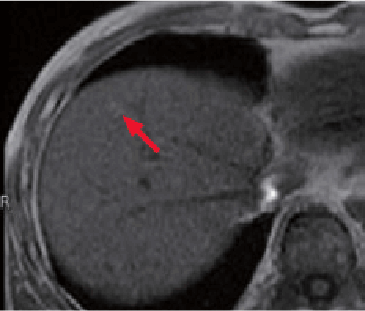

Below the liver S4/8 dome, with T1-weighted imaging a nodule (→) was found that showed a faint high signal in phase (m), and part of which showed a low signal out of phase (n). It was suggested that part of this nodule was a mass containing fat.

No images of this nodule were obtained by fat-suppressed, T2-weighted imaging (o), or diffusion-weighted imaging (p).

In the hepatobiliary phase (r) of Gadoxetate disodium(Gd-EOB-DTPA) contrast MRI, a nodule (→) 1.0 cm in diameter was found that was fixed as a distinct low-signal nodule.

This nodule was not found pre-contrast (images not shown) or arterial phase (q), and was suggested to be a hypovascular lesion.

In summary, the small nodule (→) below the S4/8 dome was diagnosed as highly differentiated HCC, with a different degree of differentiation from the principal tumor in liver S4.